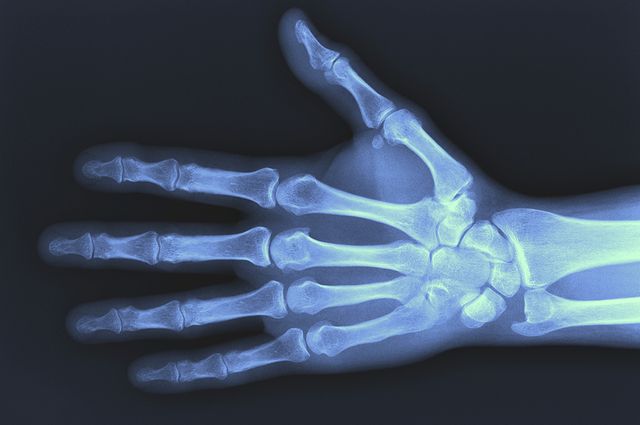

Wrist fractures are common among postmenopausal women who are younger than 65 and a new UCLA-led study suggests that they may also predict more serious fractures in other parts of their bodies later in life.

The researchers on the study, published in the November issue of the Journal of Bone and Mineral Research, found that one in five women who had experienced a broken wrist went on to suffer a non-wrist fracture during the next 10 years. They also said suggest that women who broke a wrist stood a 40 percent higher chance of breaking other bones during the subsequent 11 years compared with women who did not break a wrist.